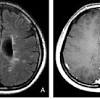

Diagnostic positif de sclérose en plaque, adapté d'après les critères de mcdonald 20170 (source : La sclérose en plaques est une maladie autoimmune qui entraine la destruction de la myéline du système nerveux central. Découvrez l'essentiel à savoir dans cet article.

Elle est due probablement à une « erreur » du système immunitaire qui se retourne contre son hôte. Cette destruction empêche les neurones d'envoyer des signaux nerveux efficaces et entraine l'apparition des symptômes de la sclérose en plaques. Vous souffrez de sclérose en plaques et souhaitez enfin trouver des informations fiables ?